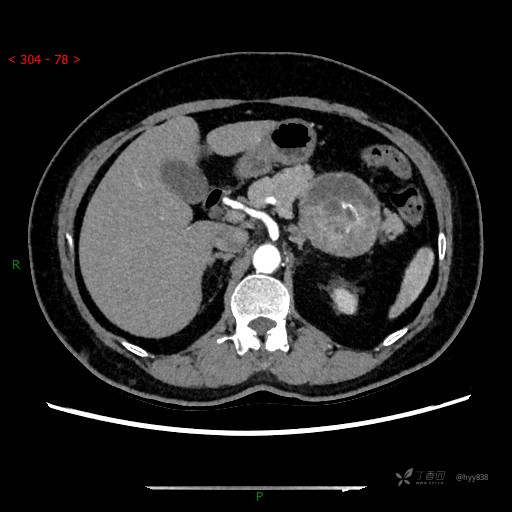

增强静脉期